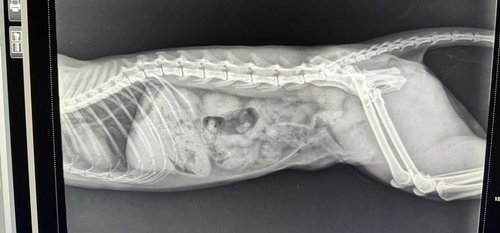

Meu gato Romeu foi atropelado dia 09/04/24 perto das 20h. No mesmo dia passou por uma cirurgia de emergência chamada “Hernioplastia” (A hérnia dele se rompeu deixando o intestino dele solto pelo corpo). Além disso o Romeu fraturou 3 ossos, sendo 2 na perna e 1 na parte de cima dele. Acontece que todos os nossos fundos foram na cirurgia de Hernioplastia, e precisamos de dinheiro para fazer a segunda cirurgia dele para corrigir os ossos quebrados…